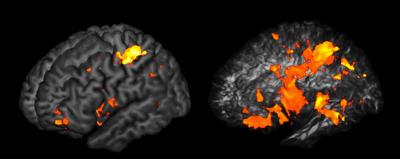

The researchers found that, rather than residing in a single structure, general intelligence is determined by a network of regions across both sides of the brain.

"One of the main findings that really struck us was that there was a distributed system here. Several brain regions, and the connections between them, were what was most important to general intelligence," explains Gläscher.

"It might have turned out that general intelligence doesn't depend on specific brain areas at all, and just has to do with how the whole brain functions," adds Adolphs. "But that's not what we found. In fact, the particular regions and connections we found are quite in line with an existing theory about intelligence called the 'parieto-frontal integration theory.' It says that general intelligence depends on the brain's ability to integrate—to pull together—several different kinds of processing, such as working memory."